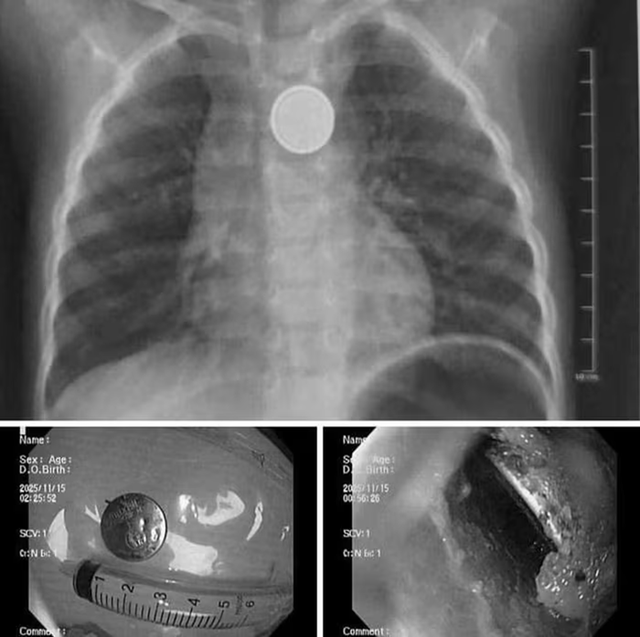

Mới đây, Bệnh viện Nhi Hải Phòng cho biết, đơn vị vừa tiếp nhận và xử trí một ca cấp cứu nguy hiểm vì nuốt phải pin cúc áo.

Bệnh nhi là bé trai 32 tháng tuổi được gia đình đưa đến viện ngay sau khi phát hiện đã nuốt phải viên pin cúc đồ chơi. Rất may, gia đình phát hiện sớm và đưa trẻ đến bệnh viện trong khoảng 1 giờ sau khi nuốt.

Tại bệnh viện, các bác sĩ đã tiến hành chụp X-quang, kết quả cho thấy dị vật kẹt tại thực quản.

Ê-kíp nội soi cấp cứu đã nhanh chóng tiến hành gắp thành công viên pin ra ngoài. Dù được cấp cứu sớm song qua quan sát trực tiếp, ê-kíp nội soi ghi nhận có vùng ăn mòn, gây loét thực quản.

Các bác sĩ cho biết, pin cúc đồ chơi có thể gây tổn thương nghiêm trọng chỉ trong thời gian rất ngắn. Do đó, việc lấy dị vật kịp thời giúp hạn chế nguy cơ thủng thực quản, nhiễm trùng trung thất và các biến chứng nặng khác.